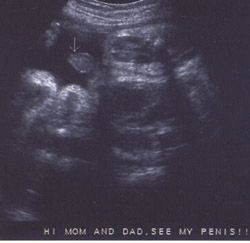

همانطور که در شکل با نشانک مشخص شده است، در هفته نوزدهم بارداری آلت تناسلی بین پاها معلوم است. فرزند شما حالا نزدیک به 240 گرم وزن دارد و قدش به 15.3 رسیده است. او حالا اندازه یک انبه است.